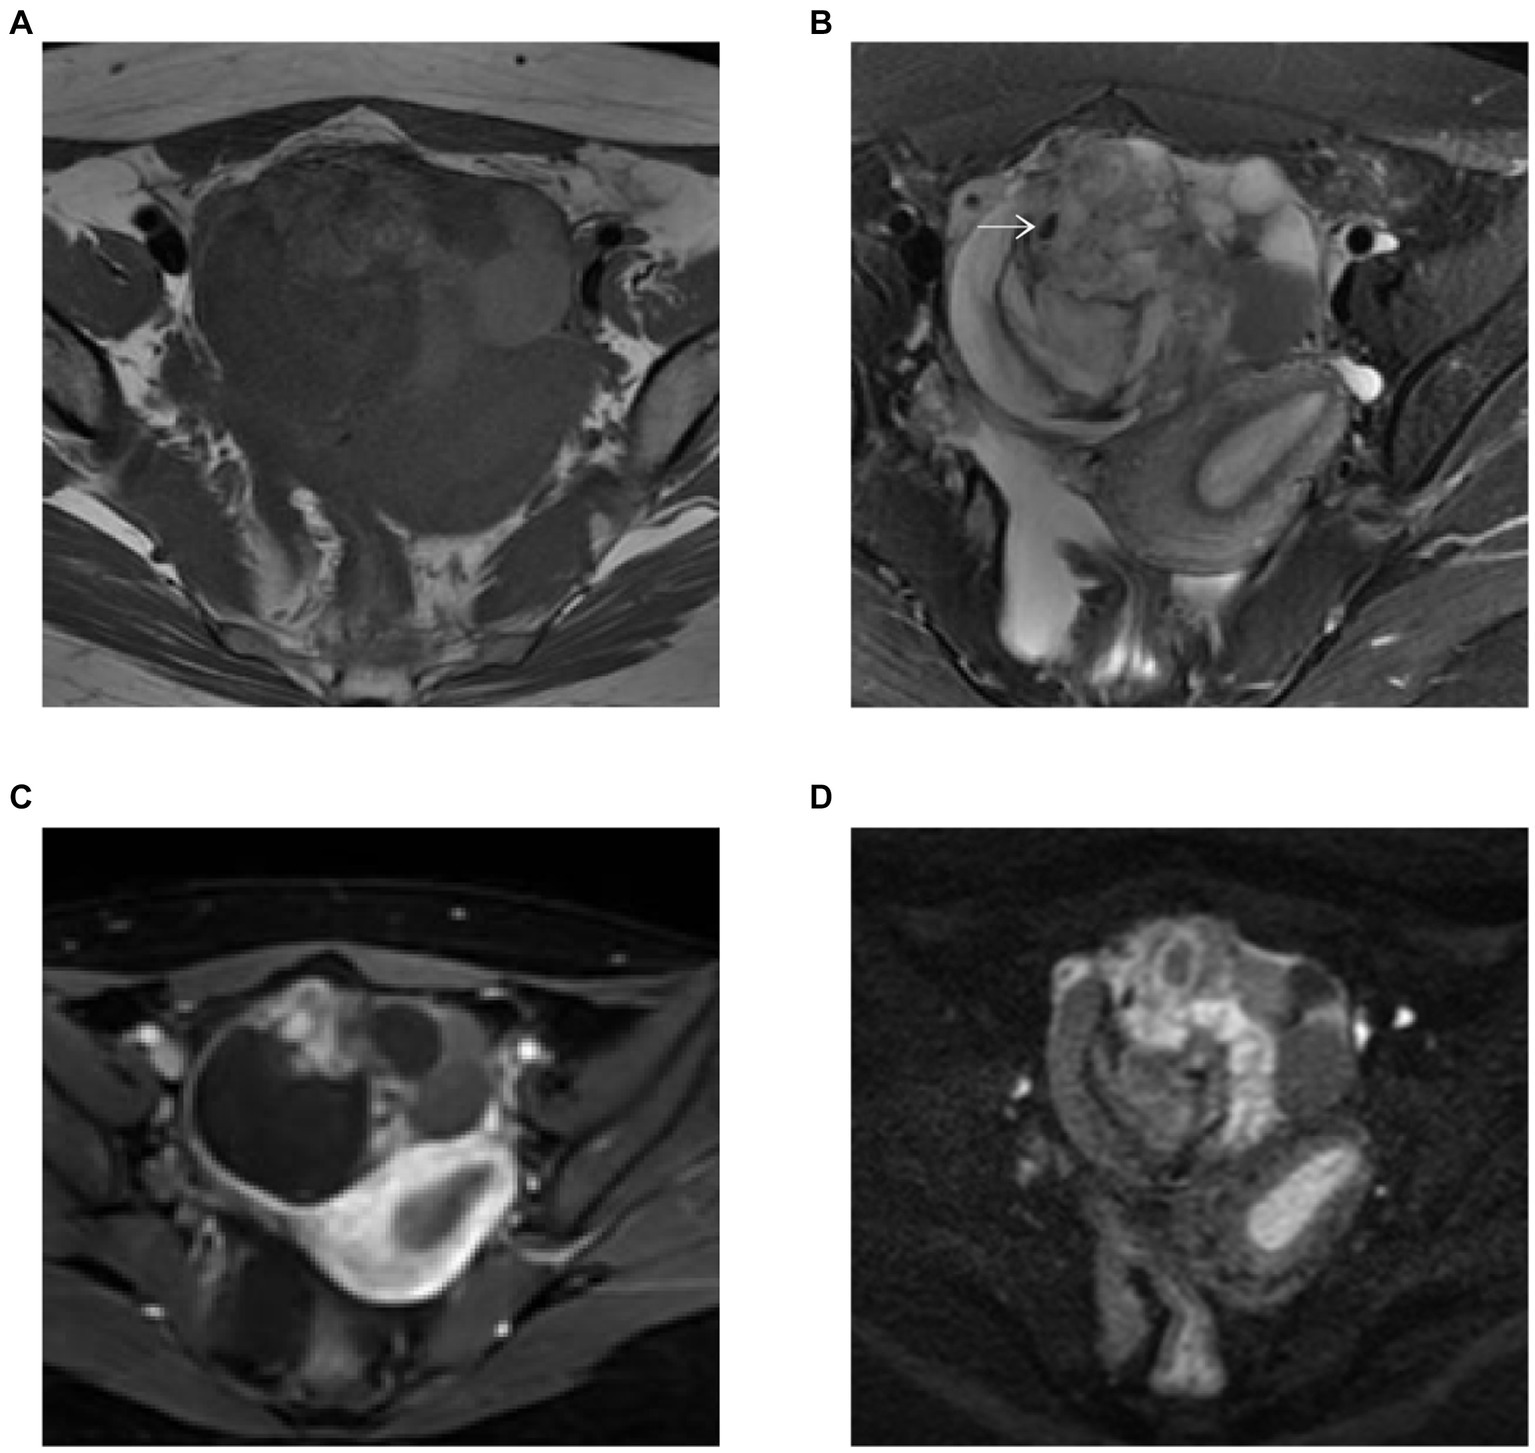

MRI showed small foci of markedly low intensity on T2-weighted images and contrast-enhanced T1-weighted images demonstrated hyperenhancement within the solid component of the mass. This area corresponded to hyperintensity on diffusion-weighted images (DWI) and hypointensity on apparent diffusion coefficient (ADC) maps. The restriction of diffusion to the solid component suggested the possibility of epithelial cancer (Figures 2A–D).

Figure 2

(A–D) Pelvis MR images. (A) T1-weighted image. MRI showed small foci of markedly low intensity (white arrow) on T2-weighted images (B) and contrast enhanced T1-weighted images demonstrated hyperenhancement within the solid component of the mass (C). This area corresponded to hyperintensity on DWI (b = 800) (D).